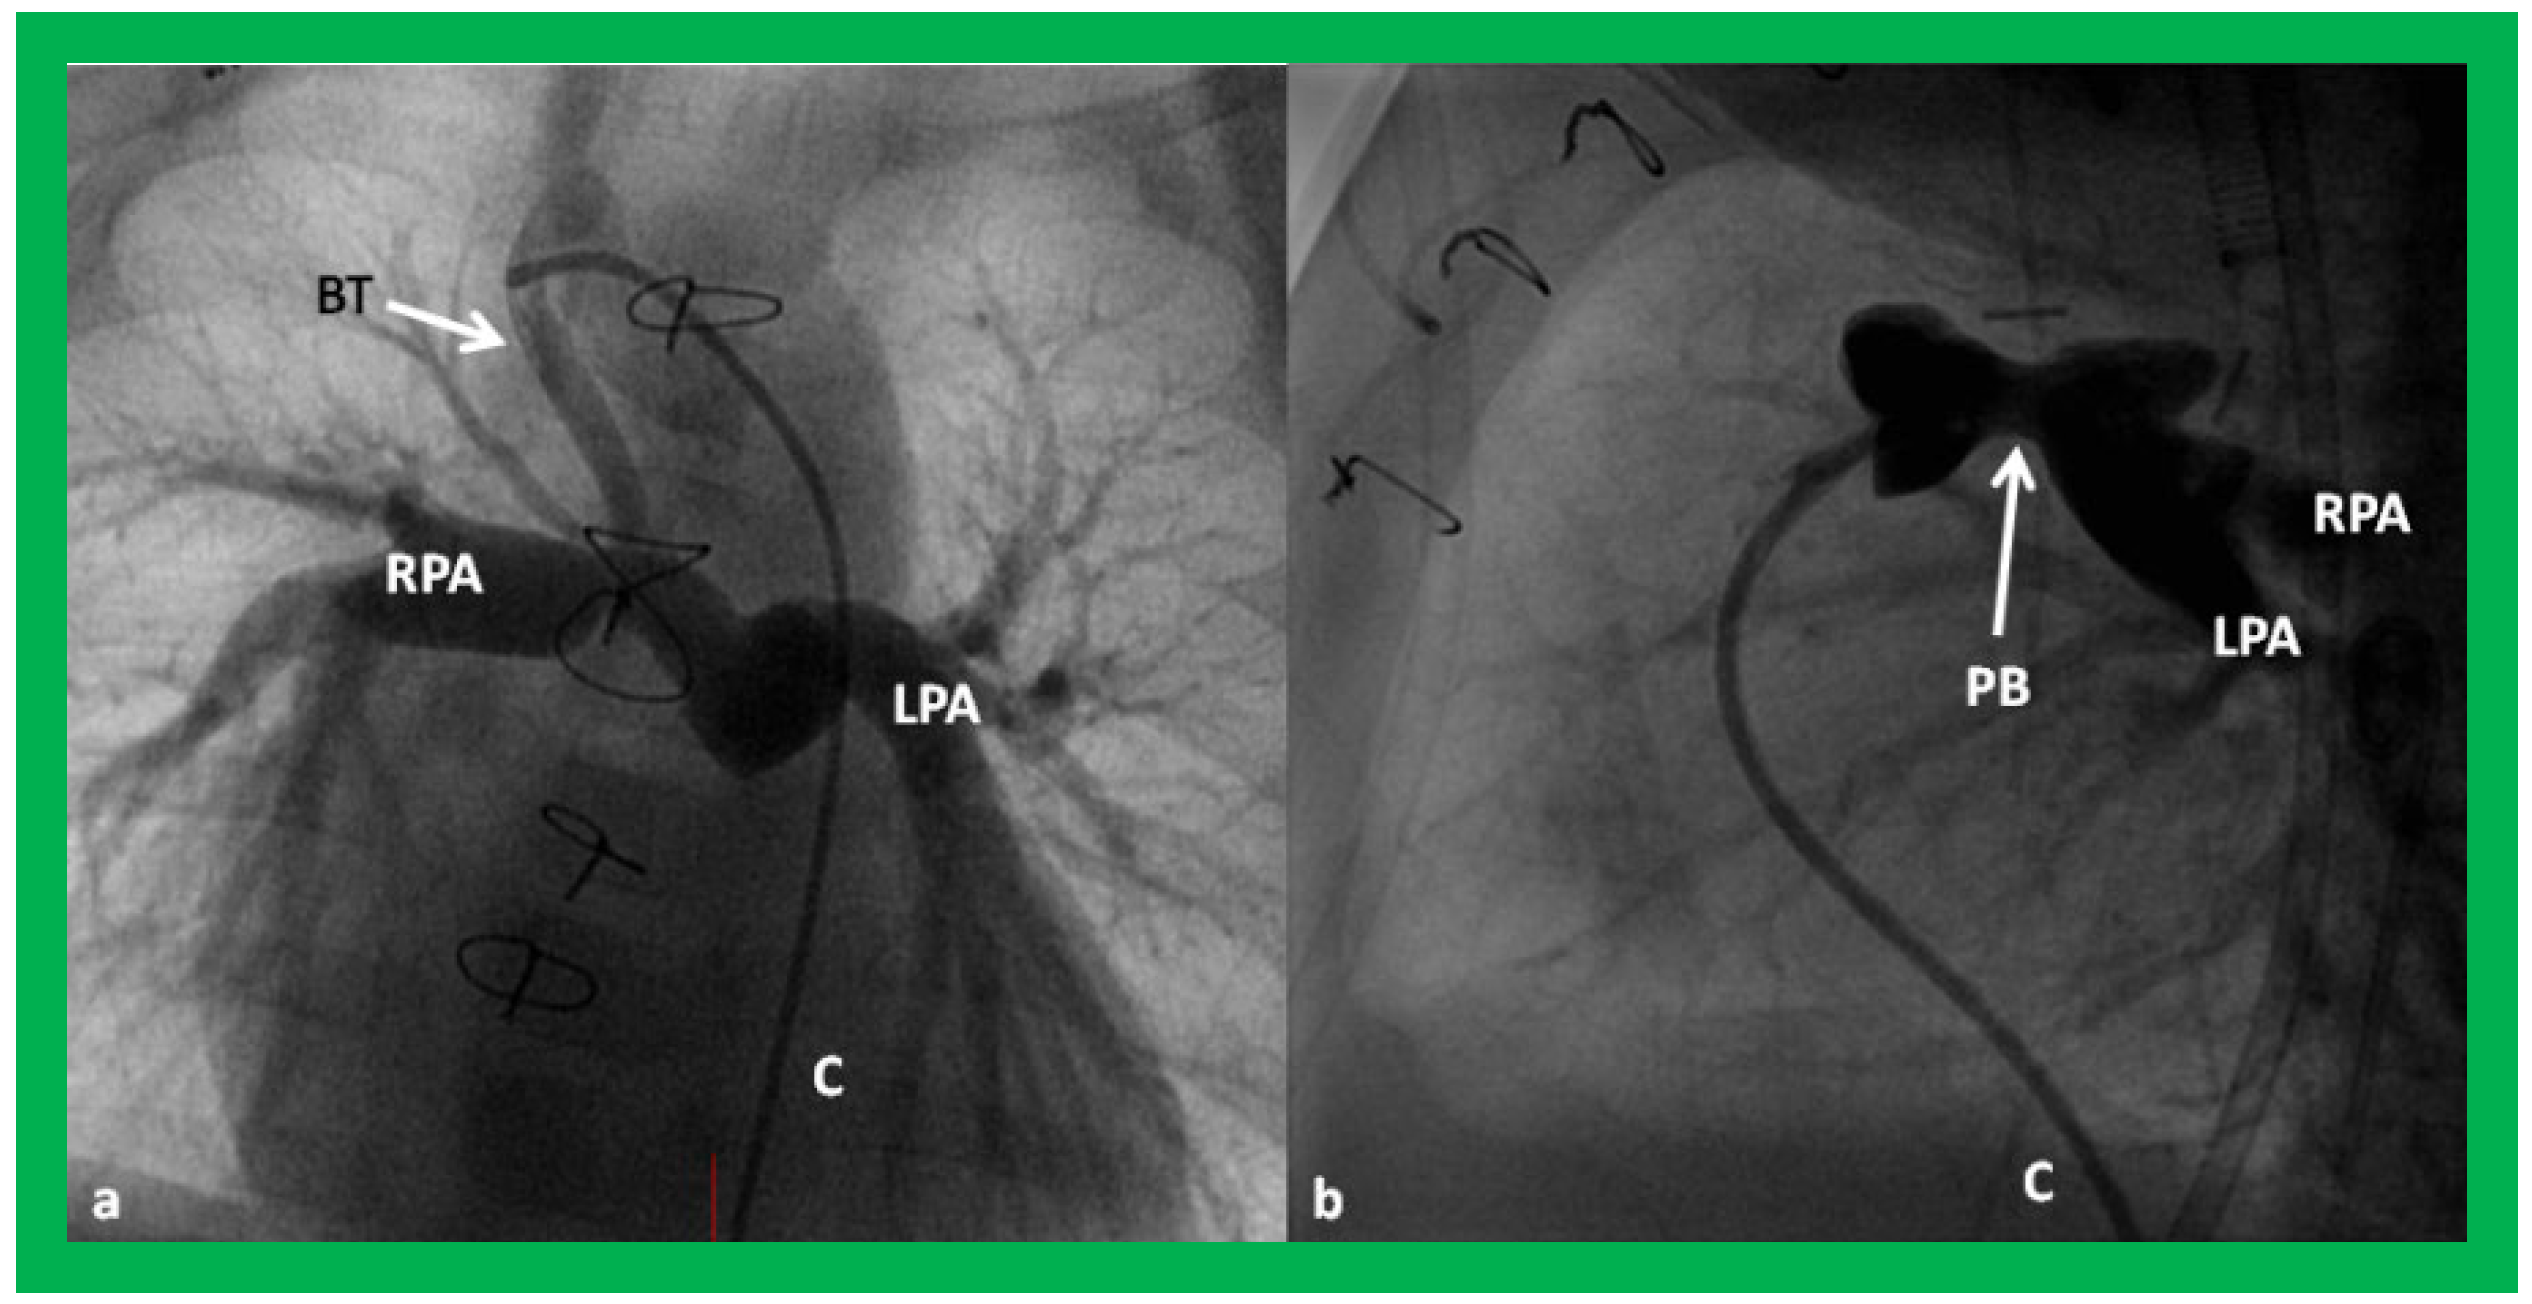

Figure 24. Selected cine frames in postero–anterior (a) and lateral (b) views, demonstrating a Blalock–Taussig (BT) shunt (arrow in a) to care for infants with decreased pulmonary blood flow (a) and pulmonary artery banding (PB) (arrow in (b)) in babies with increased pulmonary blood flow (b), respectively, during Stage I of Fontan procedure. C, catheter; LPA, left pulmonary artery; RPA, right pulmonary artery. Neonates with adequate pulmonary blood flow do not need any intervention and can go directly to Stage II at about the age of 3 months. Reproduced from Rao PS, Indian J Pediatr 2015;82:1147–1156 [36].

Angiographic counter parts of both the palliative procedures are shown in Figure 24, to have better comprehension of the anatomy of these procedures.

Angiographic counter parts of the bidirectional Glenn are shown, in Figure 29, to have better comprehension of the anatomy of the bidirectional Glenn.